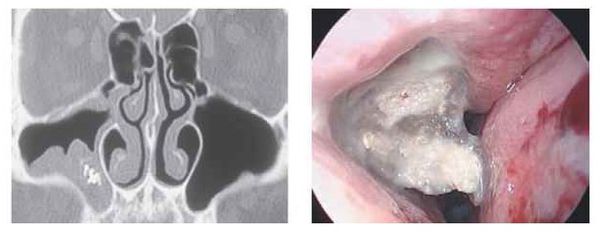

Инструментальная диагностика

Стандартные рентгенологические методы недостаточно информативны, поскольку они не могут дать объёмную послойную картину черепа, как КТ. На рентгенограммах утолщённая воспалённая слизистая оболочка пазухи имеет серый цвет, участки кальцификатов, которые образуют грибы мицетомы, — белый, а воздух — чёрный. Эти участки характерны только для мицетомы.

Мультиспиральная компьютерная томография остаётся эффективным и единственным способом диагностики мицетомы околоносовой пазухи. Использование трёхмерной реконструкции даёт представление об объёмном взаиморасположении костей, позволяет оценить состояние верхнечелюстной пазухи и зубочелюстной системы (целостность зубов, степень разрушения, цвет, положение в зубном ряду, подвижность, глубину зубодесневых каналов), а при наличии инородных тел точно показывает их форму, размер и местонахождение.

При магнитно-резонансной томографии исследование можно выполнить в двух режимах. С помощью T1-режима в центре поражённой пазухи обычно определяется образование, окружённое слоем жидкости, с низкой интенсивностью сигнала. Такое образование будет тёмным. В режиме T2 МРТ может дать ложноотрицательный результат. При этом режиме грибковое тело имеет низкую интенсивность и выглядит как область, лишённая сигнала, поэтому на снимке может быть принята за воздух.